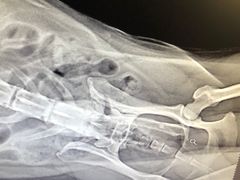

• 永康动物医院

• -永康动物医院